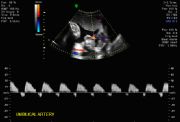

2. Normal pulsed Doppler for

valvular rhythm and function

Continuous Wave (CW) Doppler utilizes separate emitting and receiving transducers set up so that the axes intersect at a certain range determined separately for each pair of transducers. They operate continuously and therefore are not limited by a maximum detectable velocity range. All Doppler signals originating from a certain range of the area are all superimposed making actual visualization of vessels impossible. (Gill RW. Doppler ultrasound: physical aspects. Semin Perinatol 1987;11:292-99.)

3. Pulsed Doppler uses ultrasound emitted in a pulsatile fashion. Between pulses of emission, the same transducer operates as a receiver for the back-scattered echoes. Since the velocity is known and thought to be constant, it is possible to analyze the back-scattered echo alone from a particular range. A circuit selectively allows only those signals that arrive to the receiver at a specific time after the transmission. This allows a precise determination of the size of the sample volume that can be located in a specific area. (Gill RW. Doppler ultrasound: physical aspects. Semin Perinatol 1987;11:292-99) The sequence of transmit-and-receive is repeated periodically. The rate at which this is accomplished determines the performance of the pulsed Doppler system.